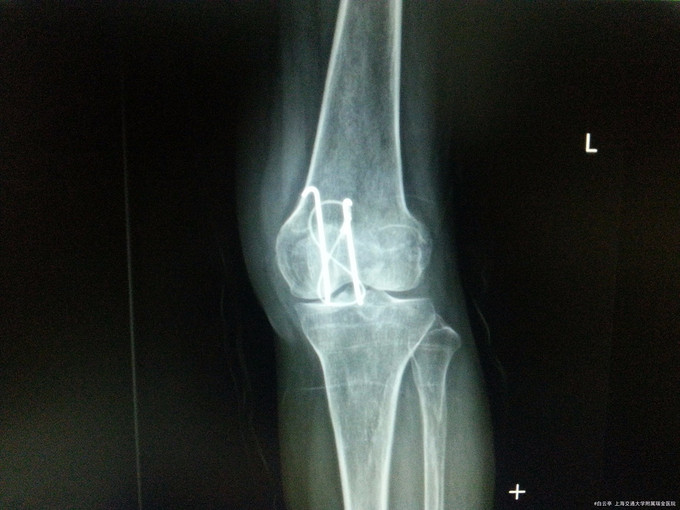

主诉:左髌骨骨折ORIF术后11个月 病史:患者,女,66y。患者11个月前因“左髌骨骨折”我院全麻下行“左髌骨骨折切开复位内固定术”。术顺,患者恢复良好予以出院。术后患者定期复查骨折愈合情况,目前患者复查左膝部平片示骨折愈合良好,患者无切口处疼痛红肿热痛、无左下肢末梢苍白、麻木等缺血表现,无畸形愈合,无肌无力等不适,现为取出内固定再次入院。

查体:左膝部可见陈旧性手术疤痕,局部无畸形,无肿胀,无压痛,皮肤无瘀斑。左膝关节活动度正常。远端肢体运动感觉皆正常。 辅检:左膝部平片:左侧髌骨骨折内固定术后改变。

诊断:左髌骨骨折术后取出内固定装置 治疗:入院评估患者骨折恢复可,行“左髌骨骨折术后取出内固定装置”